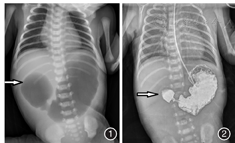

患儿,女性,3 d,因"呕吐伴腹胀3 d"于2016年3月17日由外院转入。患儿系孕6产4,孕36+3周,顺产娩出,出生体质量2.1 kg。羊水量8000 ml,Ⅰ°浑浊。出生时即口吐白沫样液体,后为黄绿色胃内容物,行上消化道造影提示:先天性十二指肠闭锁,为进一步诊治转来广东省妇幼保健院新生儿外科。入院查体:体温36.5℃,心率130次/min,呼吸45次/min。腹平,触软,肠鸣音弱。肛诊:见少量透明样黏液。入院后完善检查,胸腹正位片:见"双泡征",余腹部肠管未见充气,考虑为十二指肠梗阻,见图1。上消化道造影提示:十二指肠球部梗阻征象,符合先天性十二指肠闭锁,见图2。术前诊断:十二指肠梗阻。于2016年3月23日在气管插管全身麻醉下行剖腹探查术,术中见腹腔内少量墨绿色黏液栓,空肠距Treitz韧带5 cm处闭锁,肠管连续,空肠闭锁近端2 cm处见一直径0.5 cm大小穿孔;同时见胃、十二指肠球部明显扩张,进一步探查证实为十二指肠水平部一隔膜致十二指肠梗阻。行十二指肠吻合加空肠吻合术后,近端注入亚甲蓝检查吻合口是否通畅时,意外发现环状胰腺。术中诊断:(1)十二指肠闭锁;(2)环状胰腺;(3)空肠闭锁;(4)空肠穿孔。于空肠闭锁处连同穿孔处切除3 cm空肠,行空肠端端吻合术。游离十二指肠侧腹膜,于十二指肠水平部闭锁处切开1.5 cm,切除隔膜,间断缝合隔膜边缘,横行间断内翻缝合切开处。于环状胰腺近端横行切开十二指肠约1.5 cm,远端纵形切开十二指肠1.5 cm,行十二指肠近远端菱形间断吻合。经胃管注入亚甲蓝证实吻合口通畅。术后予以禁食、胃肠减压、抗炎、营养支持等对症治疗。术后第21天饮奶,无呕吐、腹胀不适,逐渐加奶至全奶按需,排粪正常。观察2 d后无异常,于2016年4月18日出院。随访至2017年9月2日,患儿饮食、排尿、排粪均正常,生长发育良好。

临床表现上,患儿多以呕吐、腹胀为首发症状,呕吐多为胆汁性。腹部X线片可表现为双泡征、远端肠管没有充气。胆汁性呕吐的患儿鉴别诊断主要包括:中肠扭转、远端肠闭锁、先天性巨结肠;非胆汁性呕吐的患儿鉴别诊断包括:幽门闭锁、胃窦隔膜及十二指肠狭窄等。治疗上,对于先天性十二指肠闭锁,一经确诊,应立即手术,本例患儿出生即有黄绿色胃内容物呕出,完善检查后十二指肠梗阻诊断明确,而十二指肠闭锁可能性大,转入我院后即行剖腹探查术。但值得注意的是,本病例因术中见腹腔内墨绿色黏液栓,探查发现空肠闭锁、穿孔,十二指肠闭锁。行十二指肠吻合、空肠吻合术后,近端注入亚甲蓝检查吻合口是否通畅时,意外发现环状胰腺,再次手术恢复肠管通畅性。回顾该患儿整个手术过程,笔者认为:行十二指肠闭锁手术,一定要探查近远端肠管的通畅性,以防漏诊,本例近端梗阻点——环状胰腺就险些漏诊。本例采用十二指肠菱形吻合术、十二指肠侧侧吻合术、空肠切除及空肠吻合术,术后愈合效果好。